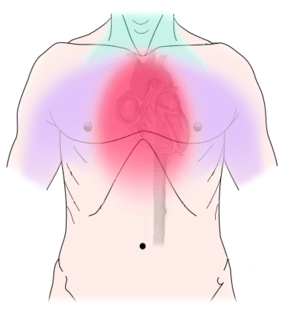

Non-dental

Non-dental causes of toothache are much less common as compared with dental causes. In a toothache of neurovascular origin, pain is reported in the teeth in conjunction with a migraine. Local and distant structures (such as ear, brain, carotid artery, or heart) can also refer pain to the teeth.[34]:80,81 Other non-dental causes of toothache include myofascial pain (muscle pain) and angina pectoris (which classically refers pain to the lower jaw). Very rarely, toothache can be psychogenic in origin.[9]:57–58

Establishing a diagnosis of nondental toothache is initially done by careful questioning about the site, nature, aggravating and relieving factors, and referral of the pain, then ruling out any dental causes. There are no specific treatments for nondental pain (each treatment is directed at the cause of the pain, rather than the toothache itself), but a dentist can assist in offering potential sources of the pain and direct the patient to appropriate care. The most critical nondental source is the radiation of angina pectoris into the lower teeth and the potential need for urgent cardiac care.[9]:68